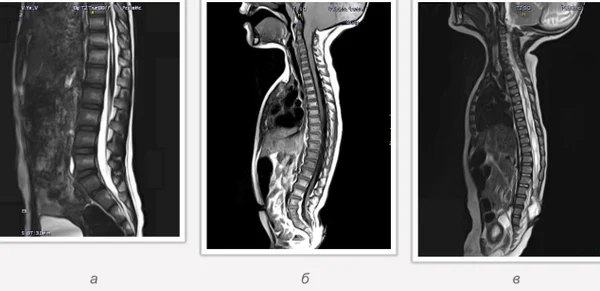

Spina bifida, спинно-мозговые грыжи, диастематомиелия, липоменингомиелолоцеле, фиксированный спинной мозгSpina bifida включают различные типы нарушения закладки и развития нервной трубки на спинальном уровне, что сопровождается незаращением дужек позвоночника и часто сопровождается одновременным пороком развития спинного мозга и его оболочек. Встречаются у 1 на 1000 – 3000 новорожденных. Могут наблюдаться в различных отделах позвоночника, но наиболее часто встречается в пояснично-крестцовом отделе. Незаращение дужек позвонков с наличием грыжевого выпячивания обозначается в литературе по разному: спинно-мозговые грыжи, spina bifida, spina bifida cystica, spina bifida vera, spina bifida typica, spina bifida aperta. Классификация spina bifida aperta: I Рахишизис. II Спинномозговые грыжи. Менингоцеле. Менингорадикулоцеле. Миеломенингоцеле. Миелоцистоцеле. Липоменингомиелоцеле. Основные сопутствующие пороки центральной нервной системы: Гидроцефалия до 65-85%. Аномалия Киари 2. Сирингомиелия.